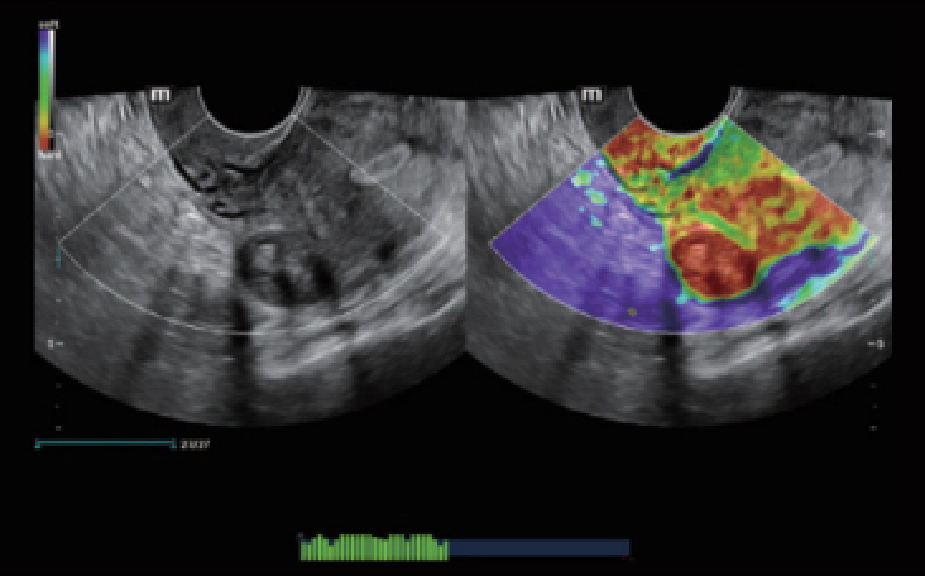

Nuewa I9, kad?nlara ve yenido?anlara y?nelik sa?l?k hizmetleri i?in ?zel olarak tasarlam??t?r ve i?ten d??a yenilik?i bir deneyim sunmaktad?r. Bu yenilikler, karma??k klinik senaryolara ili?kin derinlemesine bilgilere dayal? olarak geli?tirilmi?tir ayr?ca do?ru ve zaman?nda yan?tlar?n yan? s?ra, ola?an├╝st├╝ verimlilik ve ola?an├╝st├╝ kullan?c? deneyimi sunar.

ZST + Taraf?ndan Desteklenen Eksiksiz ??z├╝m

ZST+ platformu, ultrason evrimini temsil eden ola?an├╝st├╝ bir yeniliktir. Ultrason ?l?├╝mlerini geleneksel ???n bi?imlendirmeden kanal verilerine dayal? i?lemeye d?n├╝?t├╝r├╝r. Mekansal ??z├╝n├╝rl├╝k, zamansal ??z├╝n├╝rl├╝k ve doku homojenli?i aras?ndaki geleneksel dengeli s?n?rlaman?n ├╝stesinden gelir ve kesintisiz iyile?tirmelerle s?n?rs?z g?r├╝nt├╝leme ??z├╝mleri i?in ola?an├╝st├╝ g?r├╝nt├╝ kalitesi sunar.